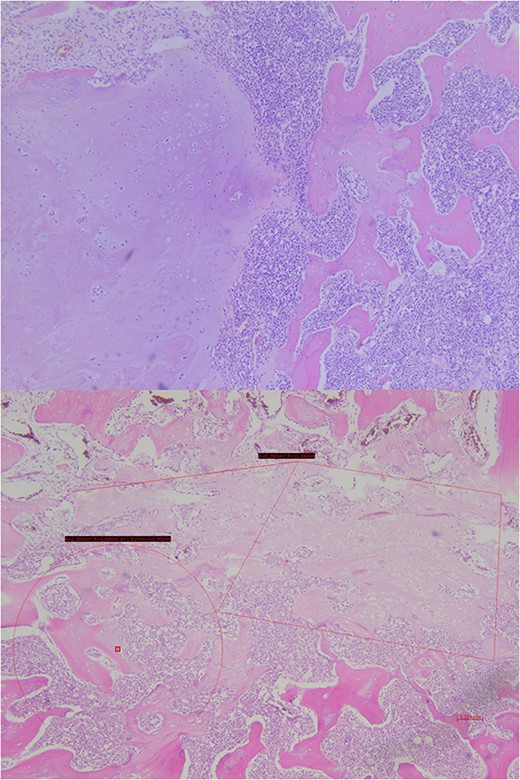

Analysis of the surgical piece established diagnosis of well-differentiated chondrosarcoma (G1) confined to T7 without extension to T6, T8, or soft tissues. Surprisingly, infiltration of high-grade neoplastic component of hematolymphoid type was present. Immunohistochemistry was consistent with DLBCL germinal center subtype (vimentin+/CD45+/CD20+/CD10+/BCL-6+/Ki67 > 80%) (Figs 6–8).

Histopathological exam, macroscopic study. A lobulated lesion (3.8 × 2.6 × 2.9 cm) involves 80% of the central vertebra (T7) and presents cartilaginous features. The lesion is confined to T7. Cavity filled with bone cement is present.

Histopathological exam, microscopic study. The lesion shows trabecular infiltration by hypercellular hyaline cartilage with cellular atypia, with no relevant mitotic activity. This tumor is confined to the central vertebra (D7) and does not extend further (R0). In the central portion, an abrupt transition to a high-grade neoplastic component of hematolymphoid type grows diffusely, composed by medium-large cells, with frequent mitosis. No extension to adjacent soft tissues or to the other vertebrae.

Immunohistochemical study shows how the described hematolymphoid neoplasia presents a immunophenotype typical of B germinal center. CD10+, CD20+, and BCL6+ are showed (from top to bottom).